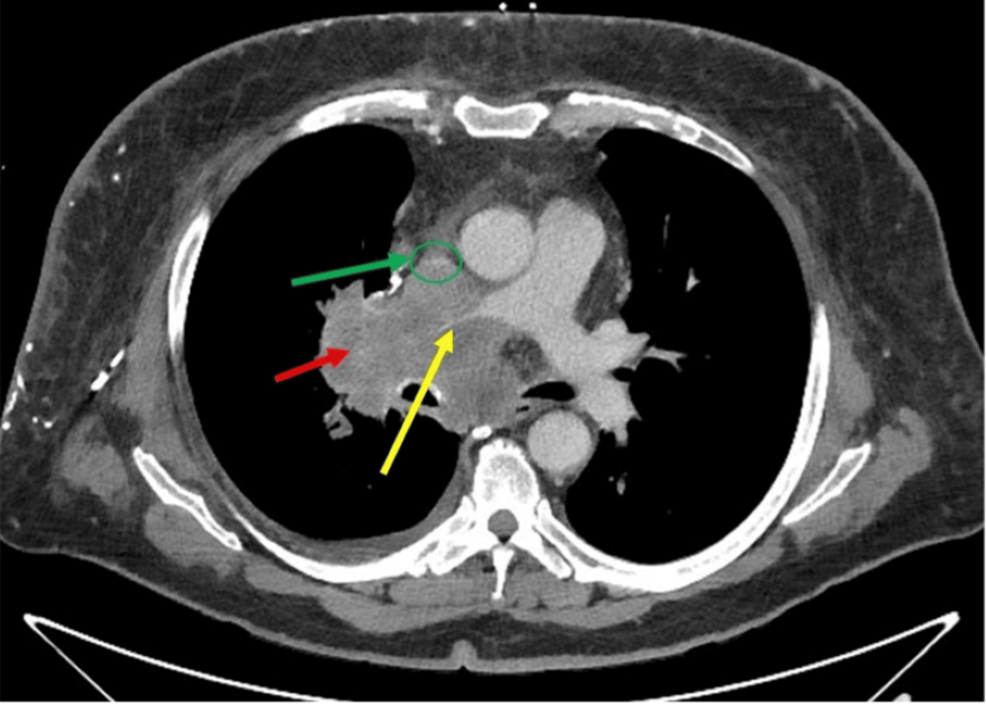

A 68-year-old obese white male patient (body mass index of 34 kg/m²) with a 50-pack-year smoking history presented to the emergency room with progressive anterior neck swelling, voice changes, and orthopnea that developed over three weeks. A chest computed tomography (CT) scan revealed a right hilar mass with direct extension into the mediastinum; the mass encased and nearly obliterated the SVC and right pulmonary artery and occluded the right upper lobe bronchus. The patient underwent balloon angioplasty of the brachiocephalic vein-SVC junction by vascular surgery under conscious sedation; however, due to involvement of the cavoatrial junction and the possibility of stent migration, they opted not to place a stent. He was started on inpatient radiation therapy and scheduled for a rigid bronchoscopy with biopsy by interventional pulmonology to obtain a histopathological diagnosis for a targeted treatment plan.